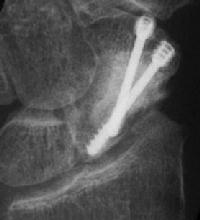

Click for larger image

Case 6. A dorsal approach for this proximal pole fracture would have been a better choice.